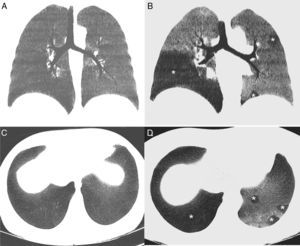

(A) minIP coronal reconstruction of the chest inspiratory CT showing homogeneous pulmonary parenchyma with uniform attenuation. (B) minIP coronal reconstruction of chest expiratory CT, showing a mosaic pattern of the pulmonary parenchyma, with areas of low density (asterisk), alternating with areas of greater attenuation. Low density areas (affecting particularly the right lower lobe and the left lung in a patchy pattern) correspond to areas of air trapping, while the areas of greater density correspond to normal pulmonary parenchyma. (C) minIP axial reconstruction of the chest inspiratory CT showing homogeneous pulmonary parenchyma. (D) minIP axial reconstruction of chest expiratory CT, showing areas of low density (asterisks), related with areas of air trapping.

We report the case of a 44-year-old woman with a history of acute myeloid leukemia, treated 6 months previously with unrelated donor HSCT, who consulted due to dyspnea and dry cough. As a complication of the HSCT, the patient had transitory cytomegalovirus viremia and cutaneous GVHD grade III, which responded favorably to treatment with corticosteroids. No parenchymal opacities were observed on chest radiograph, but chest iCT and eCT revealed a marked mosaic pattern in the pulmonary parenchyma in the expiratory phase, and multiple areas of air trapping were identified in both lungs (Fig. 1), while infectious complications were ruled out. Areas of air trapping on CT can be better viewed with the use of the minimum intensity projection (minIP), an algorithm for visualization of images that enhances areas of less attenuation. Lung function tests (LFT) showed a mild reduction (<20%) in forced expiratory volume in 1 second (FEV1) and increased residual volume (RV) (138%) with respect to pre-HSCT values. No changes were observed on fiberoptic bronchoscopy and bronchoalveolar lavage ruled out opportunistic infections. Given these findings, a diagnosis of BO was given, and the patient responded favorably to treatment with high-dose systemic corticosteroids (stabilization of functional tests).